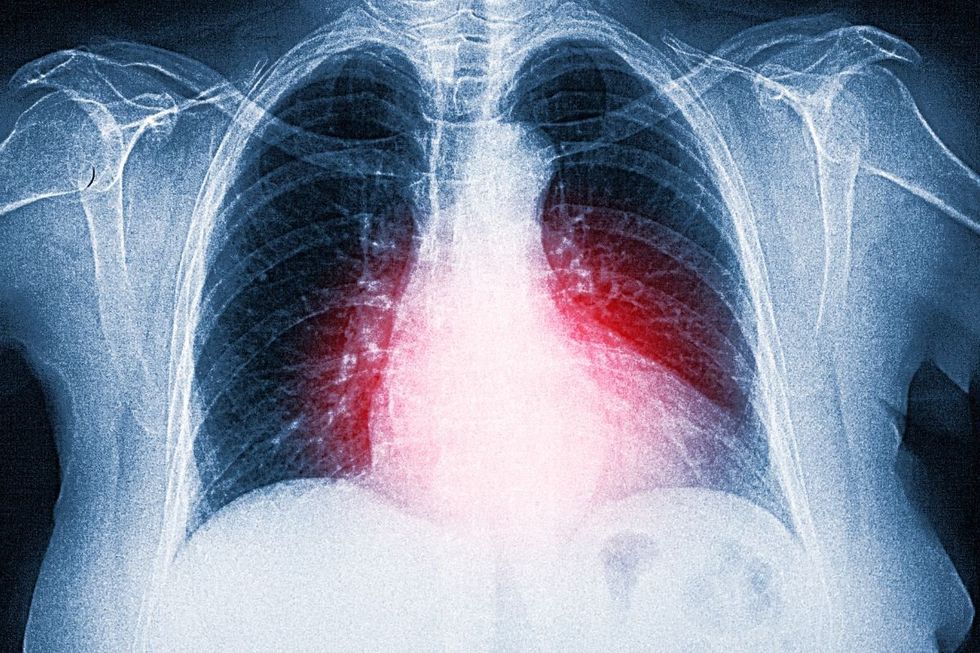

Healthy sleep patterns and diet are critical for the heart

|GETTY

Spending long periods sitting down, getting fewer than six hours of sleep, regularly eating ultra-processed foods, and living with ongoing stress all pose unexpected risks to cardiovascular health.